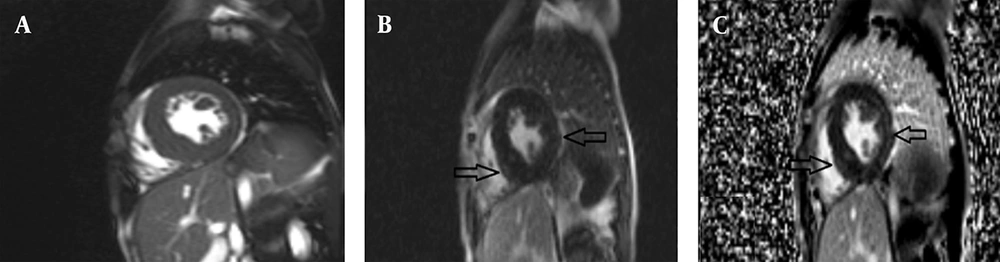

The first patient was an 18-year-old female with a height of 159 cm, weight of 40 kg, and a BSA of 1.32 m2, who presented with progressive ataxia and speech disorder, consistent with a clinical diagnosis of FA. Cardiac MRI was performed utilizing a standardized protocol that included SSFP cine imaging, LGE, and T1/T2 mapping sequences. Morphological assessment revealed concentric LVH with a maximum wall thickness of 13 mm in the basal septum, alongside interatrial septal hypertrophy. Functional analysis indicated a normal LV size with mildly reduced systolic function (LVEF = 46%) and mildly reduced RV function (RVEF = 52%); the LV Mass Index was calculated at 117 g/m2. Tissue characterization demonstrated patchy myocardial fibrosis in multiple segments on LGE imaging, while T2 mapping ruled out active myocardial inflammation or edema (Figure 1). Additionally, thoracic imaging noted mild scoliosis. In summary, the constellation of concentric LVH, patchy myocardial fibrosis, and concomitant neurologic symptoms was consistent with established cardiac involvement in FA.

Cardiac magnetic resonance (CMR) of an 18-year-old female with Friedreich’s ataxia (FA); late gadolinium enhancement (LGE) imaging showing patchy myocardial fibrosis across multiple segments: A, Short-axis phase sensitive inversion recovery (PSIR) LGE image demonstrating focal areas of mid-wall enhancement (black arrows); B, Corresponding short-axis Magnitude LGE image indicating focal areas of mid-wall enhancement, no evidence of myocardial inflammation or edema (black arrows); C, 2-Chamber Magnitude LGE image further highlighting areas of patchy fibrosis (black arrow).